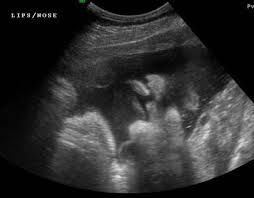

I may just be being paranoid bc i am a very paranoid person anyway. Involve the superficial tissues. Cleft lip may be detected with ultrasound beginning around the 13th week of pregnancy. Best seen on coronal images of the upper lip.

Best seen on coronal images of the upper lip. Type 2 unilateral. My ultrasound tech said that she can easily spot a cleft lip but a cleft palate is much harder to see i am sure you could google ultrasound pics with cleft lips and see some pictures. An explanation why the cleft was mistakenly considered to be one on the left side could be that the cleft was located near to the midline and the 2d ultrasound frontal view was an oblique frontal view figure 1.

Midline sagittal views normal. Ultrasound pic looks like cleft lip and im freaking out. Ultrasound of cleft lip and palate. What does cleft lip look like in ultrasound i think you can see it easily especially the 3d 4d one.